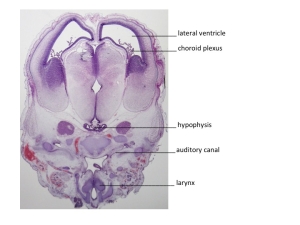

Stage

Stage:

CfS

Day:

d6